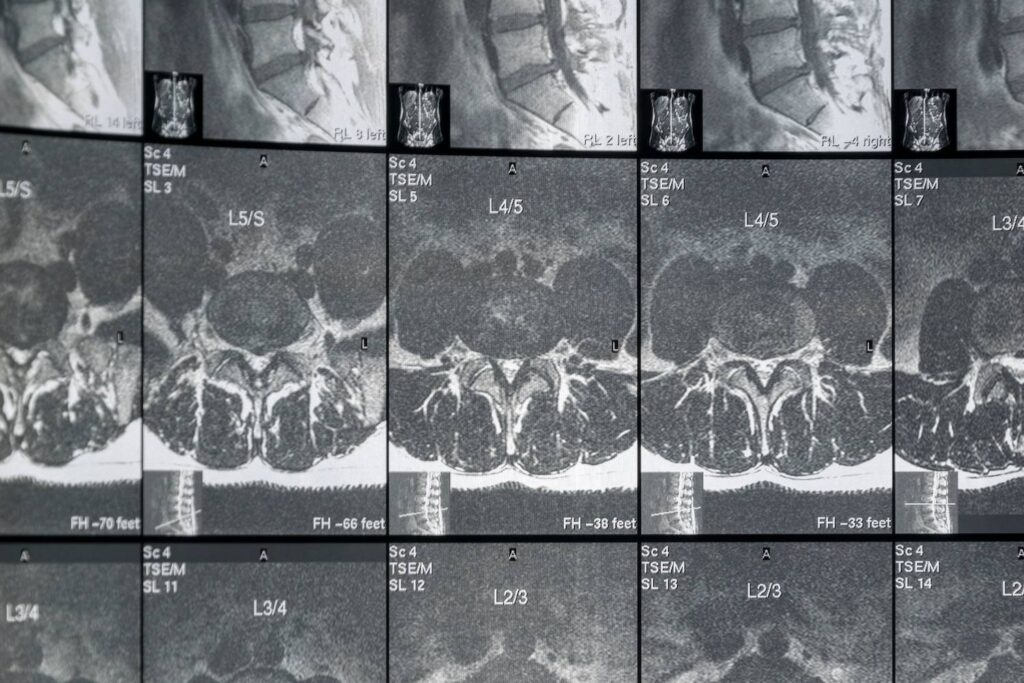

Nach der körperlichen Untersuchung kann der Arzt die Diagnose mit Hilfe von bildgebenden Verfahren wie Röntgenaufnahmen, CT-Scans oder MRT-Scans bestätigen. Es gibt auch Fälle, in denen ein Arzt einen Nervenleitungstest oder eine Elektromyographie durchführen kann, um zu prüfen, ob die Nervenwurzel geschädigt ist. Die häufigste bildgebende Untersuchung zur Diagnose der Erkrankung ist die MRT, die detaillierte Bilder der Weichteile im unteren Rücken liefert.

Die MRT-Untersuchung kann mit einem in die Blutbahn injizierten Kontrastmittel durchgeführt werden, aber das ist nicht immer der Fall. Mit dem Test kann festgestellt werden, welche Bandscheibe betroffen ist, wenn es eine Nervenkompression gibt. Mit dem MRT-Scan können auch Rückenmarkstumore, Abszesse und knöcherne Überwucherungen erkannt werden.